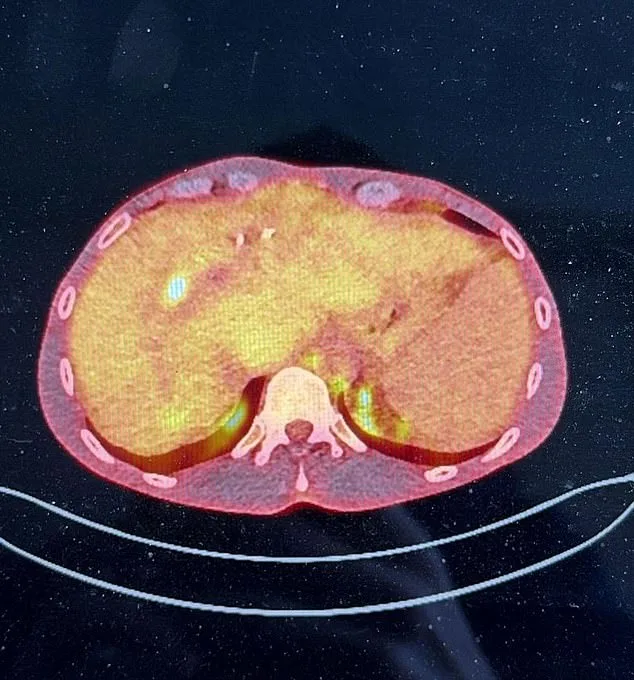

James Conradi, 38, is locked in a desperate race against time after being denied a life-saving liver transplant by the NHS. A father of one, he was recently diagnosed with cholangiocarcinoma, a rare liver cancer linked to his pre-existing autoimmune disease, primary sclerosing cholangitis (PSC). The NHS has ruled him ineligible for a transplant because one of his tumors measures just 4mm beyond the 2cm threshold required for the procedure.

Conradi's wife, Laura Kay, 41, a padel influencer, revealed the heartbreaking criteria that have left her husband with no NHS options. 'Patients like James are not eligible if their tumors exceed 2cm,' she said. 'His is 4mm over, and that disqualifies him.' Without a transplant, Conradi faces inevitable death. His liver, already severely damaged by PSC, cannot tolerate cancer treatment, leaving him with no alternative but to seek a private solution.